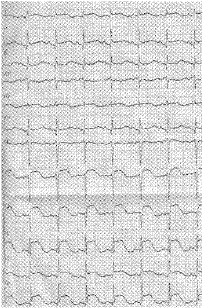

患者,女,74岁,慢性支气管炎病10余年,高血压病20余年,最高血压达180/110mmHg,坚持服用替米沙坦80mg qd,波依定5mg qd,血压控制在120~130/70~85 mmHg左右,否认糖尿病、高脂血症,无烟酒嗜好。3年前出现活动后心悸、气促,休息后缓解。3小时前患者大便后突胸骨中下段及剑突下疼痛,伴大汗、自服速效救心丸、硝酸甘油症状稍减轻,急诊入院,查体:T36℃,R20次/分,P68次/分,BP90/60mmHg,查体合作,神志清楚,口唇无紫绀,颈静脉无怒张,双肺底可闻及散在的湿啰音,心界向左下扩大,心率68次/分,心律整齐,心音有力,各瓣膜听诊区未闻及杂音,腹软,无压痛及反跳痛,肝脾肋下未触及,Murphy's征阴性,肝脾肾区无叩痛,移动性浊音阴性,未闻及血管杂音,双下肢无水肿,双侧生理反射对称存在,病理反射未引出。急诊心电图(图1)示:窦性心律、下壁心梗、急性广泛前壁心肌梗死。血常规示血小板计数753×109/L,白细胞计数20.69*109/L、中性粒细胞比值77.6%,红细胞计数5.24*109/L,电解质示血钾3.4mmol/L;脑钠肽10240pg/ml;肌钙蛋白0.528ng/ml;D-二聚体1.82mg/L;胸片示主动脉迂曲、增宽、钙化。入院立即给予拜阿司匹林+氯吡格雷+GPⅡb/Ⅲa受体拮抗剂(替罗非班)抗血小板等治疗,发病4h行急诊冠脉造影,结果示:冠脉分布为左优势型,LM未见明显狭窄,LAD近段内膜不光滑,狭窄约20~30%,中段可见心肌桥,收缩期压缩约70%,LCX内膜不光滑,RCA开口处可见75%狭窄,未见侧枝循环。术后继续予拜阿司匹林+氯吡格雷双联抗血小板、低分子肝素钠抗凝、瑞舒伐他汀调脂、单硝酸异山梨酯扩管、头孢哌酮钠舒巴坦钠抗感染等治疗;住院期间反复查血小板均在700×109/L以上,骨髓涂片示:全片共见巨核细胞25个,其中幼巨11个,颗粒巨5个,产板巨7个,裸巨2个,可见多园核巨核细胞,血小板成堆分布(图2)。诊断考虑原发性血小板增多症,在原有治疗基础上加用羟基脲抗血小板增生等治疗后,复查血常规血小板计数逐渐下降,未在发作胸痛及心衰后患者出院。

图1Ⅱ、Ⅲ、avF导联ST段弓背抬高≥0.1mv,V1V6导联ST段弓背抬高≥0.3mv,T波倒置